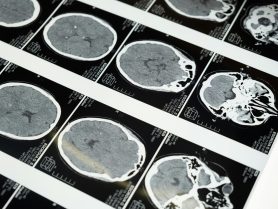

US Travel Creator Praises Indian Healthcare After Recovery in Rishikesh, Calls It ‘Far Superior’ to the West

An American travel content creator has gone viral on social media after sharing his experience with India’s healthcare system and describing it as more accessible and effective than many Western models. Charlie Evans,... more